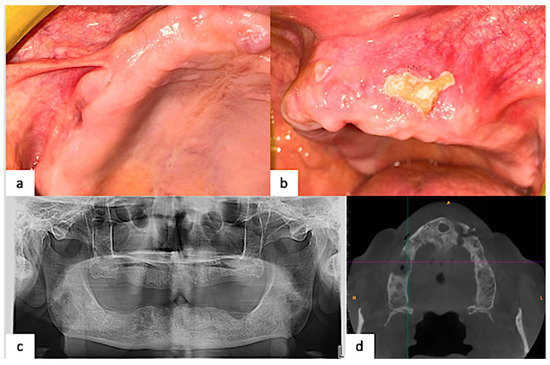

2.3. Clinical Findings and Diagnostic Assessment

2.4. Therapeutic Intervention

2.5. Follow-Up